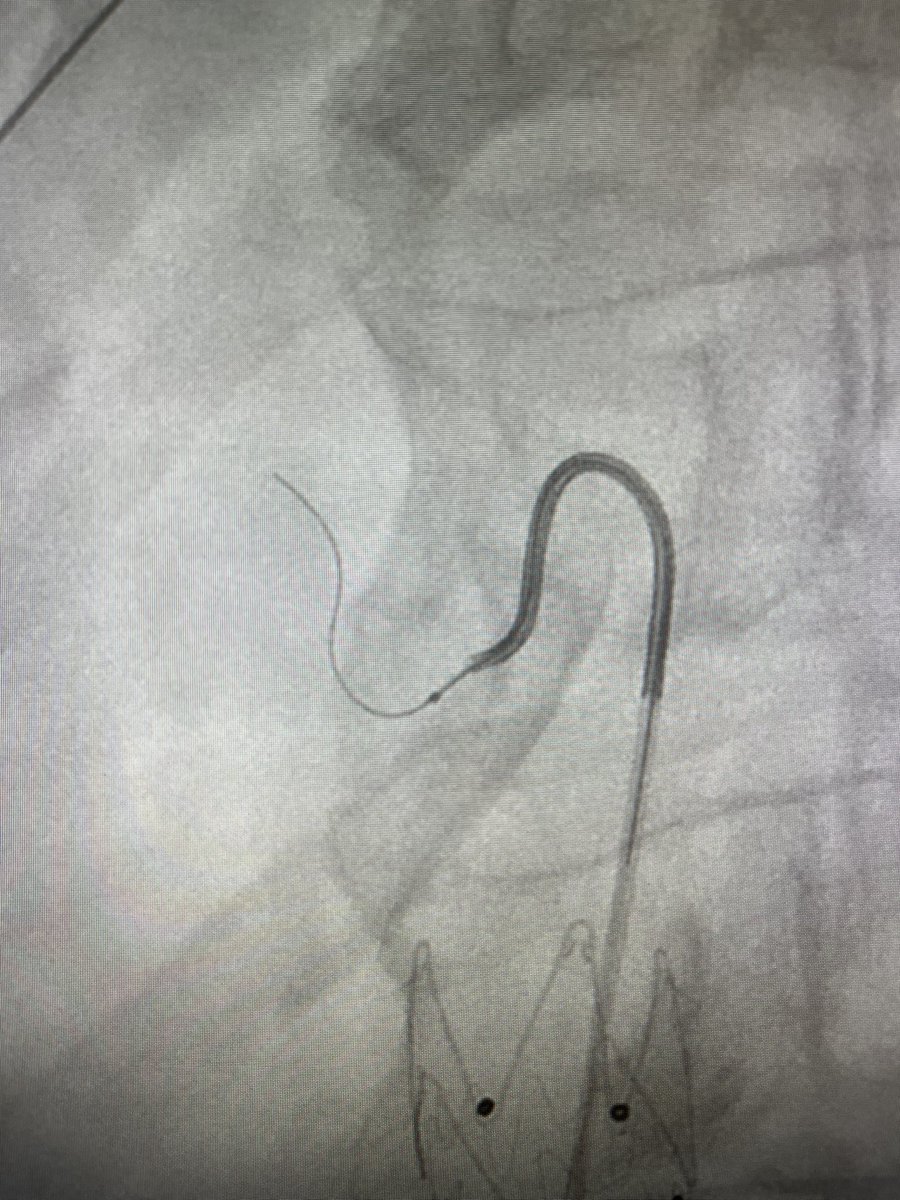

Takeoff of LGA right after celiac stenosis. J- and C-shaped microwire kept failing. Remembered preshaping Shepherd’s crook, published from IRs in Korea. 🙏🙌🙌 The Dotter Institute Yilun Koethe, MD SIR RFS

Takeoff of LGA right after celiac stenosis. J- and C-shaped microwire kept failing. Remembered preshaping Shepherd’s crook, published from IRs in Korea. 🙏🙌🙌 <a href="/dotter_IR/">The Dotter Institute</a> <a href="/DrKoethe/">Yilun Koethe, MD</a> <a href="/SIRRFS/">SIR RFS</a>